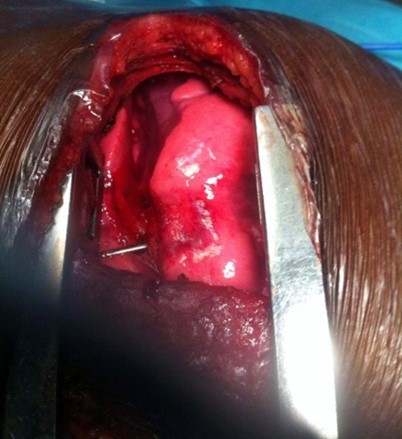

AD, aged 10, with no particular pathological history, was referred to us for the management of a post-traumatic intrapulmonary foreign body. The traumatism would have occurred one month earlier, during a playful accident. He would have received from his brother, at the level of the left hemithorax, a blow with the metal tail of a comb. The latter would then have been torn off by the child but without the tail. This would have caused a minimal wound, associated with an intense chest pain, without dyspnea, or cough, justifying local care and treatment with analgesics. The incident was withheld from parents. On admission, there was a punctiform scar in the 2nd left intercostal space, about 5 cm from the sternal border. The pulmonary fields were free. The rest of the exam was normal. The biological results were normal. A first chest x-ray showed a metal rod, oblique downwards, backwards and inwards, going from the 5th to the 11th left costal arch (Figure 1). The computed tomography scan of the chest showed the metal rod in the lung parenchyma. It was approximately 105 mm long and stayed away from the heart and the great vessels. There was no pulmonary parenchymal abnormality, pleural effusion or obvious bone lesion (Figure 2). Two subsequent X-rays showed its migration downwards, inwards and backwards with an upper pole sitting opposite the posterior arch of the 8th rib. A left posterolateral thoracotomy approach allowed the removal of the metal rod lodged in the lower lobe of the lung (Figure 3). The postoperative period was unremarkable. The ablation of the drains was carried out on the5th postoperative day. The patient was discharged on the 8th day. Reviewed in the6th postoperative month, his examination was normal.

Figure 3.Foreign body visible within left lower pulmonary lobe through posterolateral thoracotomy